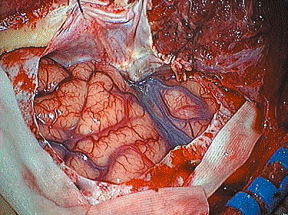

Intraoperativer Aspekt eines Optikusscheidenmeningeoms (Typ 2a) mit Durchwachsen des Meningeoms durch den Sehnervenkanal in den intrakraniellen Raum; Operation über einen Kopfzugang mit Dekompression des Kanals und intraduraler Tumorentfernung. Sekundär Bestrahlung des intraorbitalen Anteils (Tumor in der Augenhöhle).